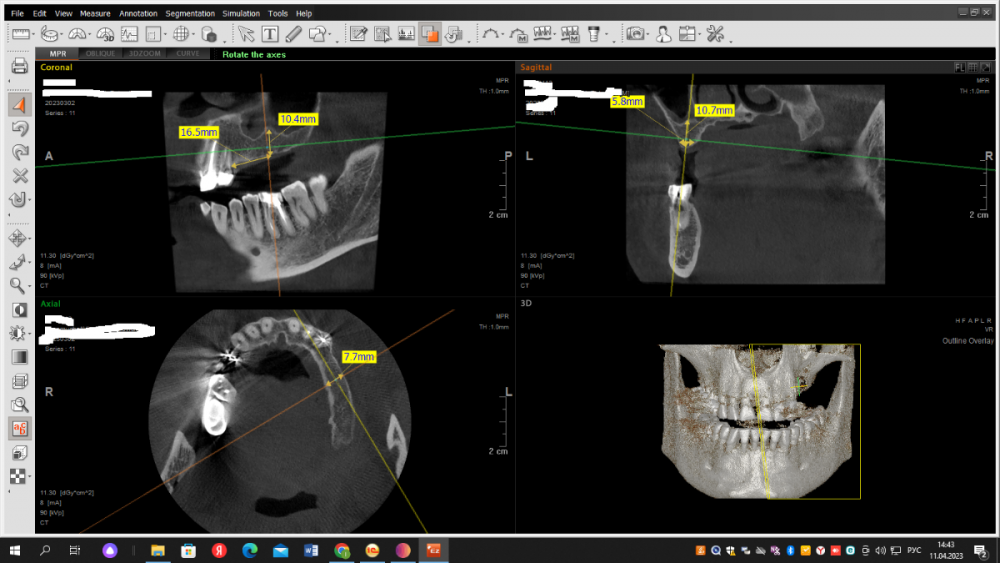

Dr T Опубликовано 13 мая, 2023 Поделиться Опубликовано 13 мая, 2023 (изменено) Уважаемые стоматологи, прокомментируйте, пожалуйста, что можно порекомендовать в данной ситуации доктору нашей клиники. Предполагался мост на имплантатах зубы 24-26, мужчина, 45 лет. Доктор выбрал 2 имплантата 4.2 по 8мм. Кость по КТ хорошая, но в ходе имплантации что-то пошло не так. В конечном итоге, один имплантат стал близко к зубу и то со второго раза и подсыпалась косточка. Можно ли оставлять как есть или слишком близко к зубу и что делать? Имплантация была 2 недели назад. На снимках первая установка и потом после попытки выпрямить 24 имплантат. Изменено 13 мая, 2023 пользователем Dr T Ссылка на комментарий

Dr T Опубликовано 14 мая, 2023 Автор Поделиться Опубликовано 14 мая, 2023 (изменено) @Irouil Насколько я понимаю, расстояние между имплантатом и зубом должно быть минимум 1,5 мм, чтобы предотвратить ишемию и резорбцию кости? Мне кажется, что легче удалить имплантат сейчас и переставить, прежде чем он интегрируется, и это предотвратит возможную потерю зуба, имплантата или того и другого. Если его оставить для наблюдения за симптомами, будет сложнее решить проблему после его интеграции, плюс гарантированные трудности с протезированием? Стоимость не проблема. Вопрос как лучше для пациента? Изменено 14 мая, 2023 пользователем Dr T Ссылка на комментарий

Irouil Опубликовано 14 мая, 2023 Поделиться Опубликовано 14 мая, 2023 @Dr T лучше для пациента сделать все правильно, а Вы говорите, что Вам кажется 4 часа назад, Dr T сказал: что легче удалить имплантат сейчас и переставить "Легче" это не "лучше", у пациента имплант уже стоит и если Вы его удалите - точно столкнёте пациента с повторной операцией, дополнительным ожиданием... Чтобы дать точный ответ нужно провести внутриротовые замеры и сопоставить данные с КТ, но ВЕРОЯТНЕЕ ВСЕГО лучше для пациента, в отсутствии симптоматики, протезировать его так, ибо условия позволяют, соблюдая современные протоколы, получить качественный результат. Лично я бы именно так и поступил. НО! Я у Вас в клинике не работаю, а что и как будет делать лечащий врач я не знаю. Более того - Вы тоже не знаете, ибо Вы не являетесь лечащим врачом пациента. Поэтому все эти обсуждения, на мой взгляд, развивать бесполезно - возможно у Вас работает первоклассный специалист, который действительно не создал себе нерешаемых проблем на следующий этап лечения и который уверен в качествах своего коллеги протезиста, способного завершить кейс в выбранном русле. Возможно и иное - доктор создал сложную ситуацию, которую ни у него, ни у его коллег по клинике способностей решить не хватит и стоит все снести и переделать пока не поздно. Выбор делать только Вам, здесь на форуме искать толковых советов бесполезно. P.S. 1.5 мм между имплантом и зубом - это крайне устаревшие данные, вроде той, что минимальная толщина альвеолярного гребня для имплантации должна быть 6.5мм. На сегодняшний день мы отталкиваемся от значений 0.8 мм для многокомпонентных имплантов. Ссылка на комментарий